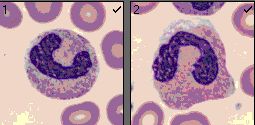

- Pelger Huet-Anomalie, seltene angeborene Auffälligkeit, die reifen neutrophilen Granulozyten haben nur 2 Kernsegmente (heterozygote Form) oder nur einen Kern (homozygote Form). Davon sind Pseudo-Pelger abzugrenzen, die im Rahmen einer hämatologischen Erkrankung eine Störung der Segmentierung des Kernes zeigen.